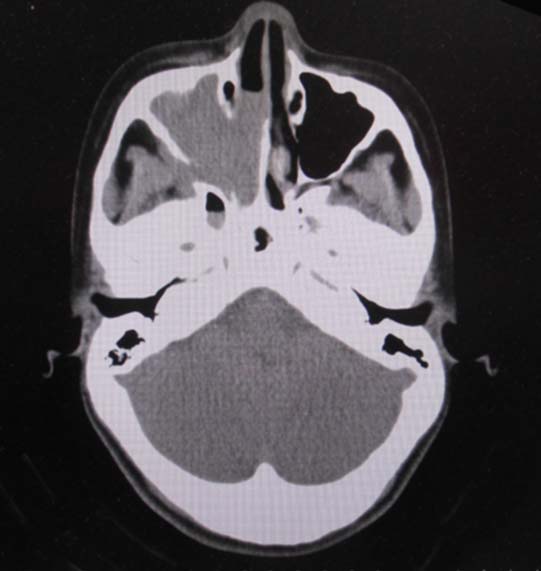

CT所見

副鼻腔腫瘤生検組織

日本病理学会中部支部交見会のスライドより。(S.Suzuki Dr.)